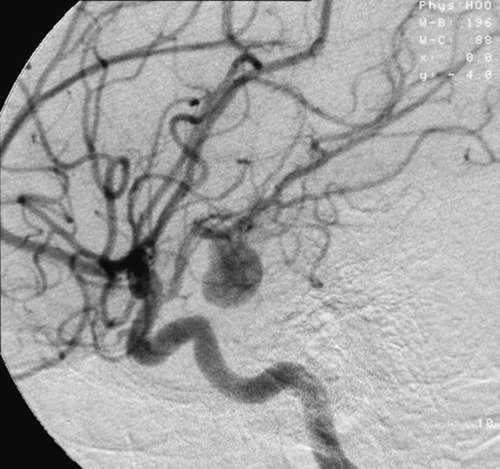

როდესაც ანევრიზმაზე ვსაუბრობთ საქმე თავის ტვინის მკვებავ არტერიებს ეხება – ვისაუბრებთ პროცესზე, რომელიც თავის ტვინის სისხლის მიმოქცევის სისტემაში მიმდინარეობს.